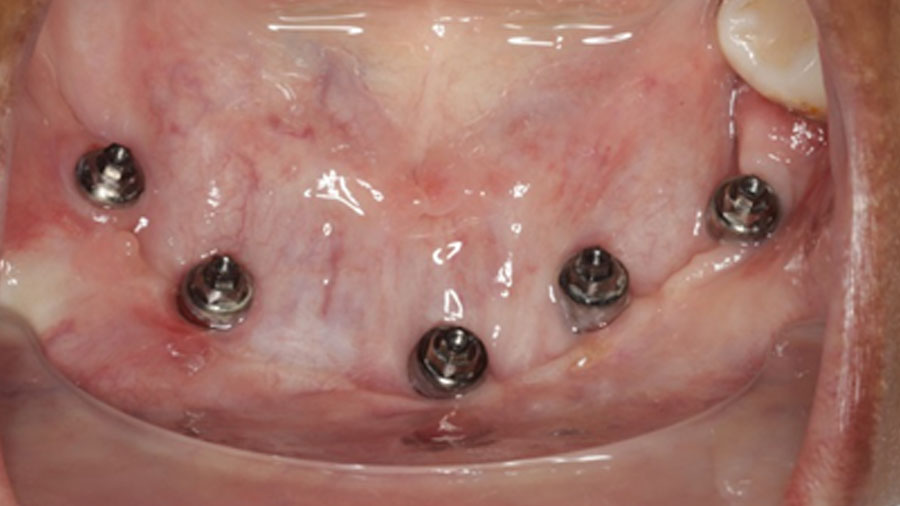

6 months later ossicle maturation is complete and planning and execution of implant placement can be done in the traditional manner.